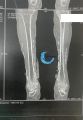

| − | + | == Radios & [[Scanner]] de jambe avec calcifications cutanées dans les ulcères== | |

Radios & Scanner de jambe avec calcifications cutanées dans les ulcères